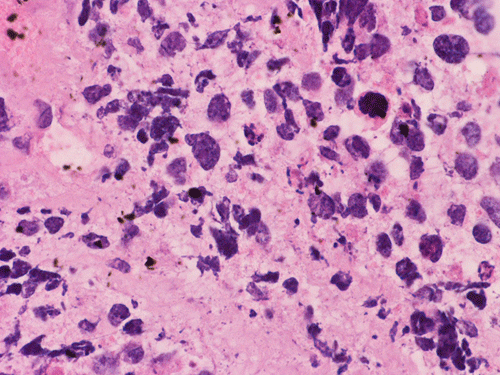

On permanent sections, there is extensive necrosis (Panel G) and there are numerous small islands of pyknotic or apototic nuclei (Panel H). In non-necrotic areas, the nuclei are large and pleomorphic. There are numerous mitotic figures (Panel I). Nuclear wrapping (Arrow in Panel J) is readily seen. The tumor is focally positive for synaptophysin, neurofilament proteins, glial fibrillary acidic protein, and diffusely positive for antibody BAF47.

Large cell (anaplastic) medulloblastoma is characterized by large, vesicular nuclei that are 5 times or more the size of a red blood cell. Marked variation in nuclear size and contour, and multinucleated, bizarre giant cells are other features. In particular, nuclear hugging or nuclear wrapping which refers one nucleus being surrounded by other nuclei as illustrated in this cases is a classic features of large cell medulloblastoma. In contrast to the classic type of medulloblastoma, the nucleoli are prominent, necrosis is prominent and extensive, extensive apoptotic or pyknotic cells are common. Large cell medulloblastomas have numerous mitotic figures that far exceed what would be expected in a classic medulloblastoma. Attempts has been made for a grading system of anaplstic changes in medulloblastoma 1 but the value of this system still has to stand the test of time 2, 3.